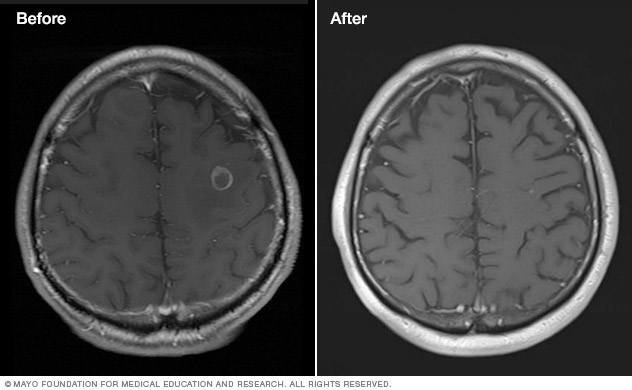

Brain tumor before and after Gamma Knife treatment

Malignant brain tumor before (left) and 111 months after Gamma Knife stereotactic radiosurgery (right)